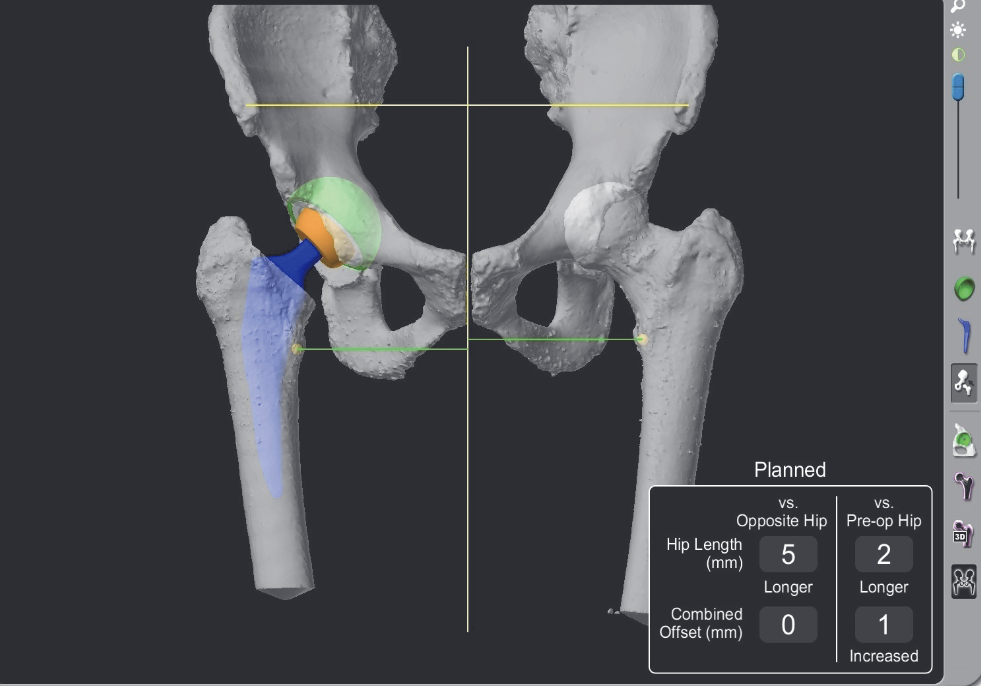

CT navigation

Migliorini et al Eur J Med Res 2023

- meta-analysis of CT navigation versus conventional in THA

- CT navigation reduces LLD